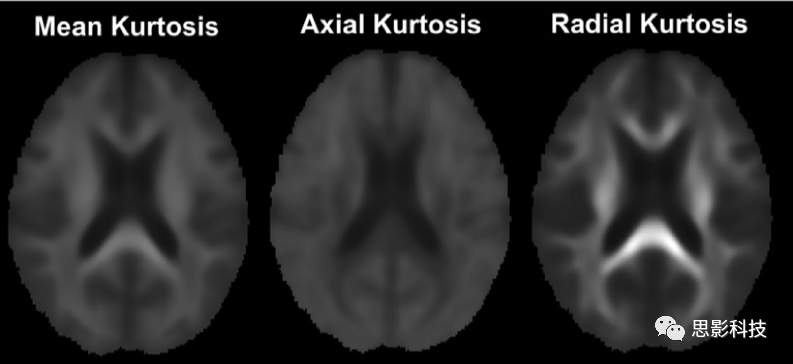

1)彌散峰度成像(diffusion kurtosis imaging,DKI)

擴(kuò)散峰態(tài)成像(DKI)是一種表征非高斯擴(kuò)散的成像方法,即通過(guò)估計(jì)位移分布的過(guò)度峰態(tài)來(lái)表征非高斯擴(kuò)散,計(jì)算出平均峰度(MK)、軸向峰度(AK)、徑向峰度(RK)等標(biāo)量指標(biāo)進(jìn)行進(jìn)一步基于體素的統(tǒng)計(jì)分析。

圖例 DKI指標(biāo)